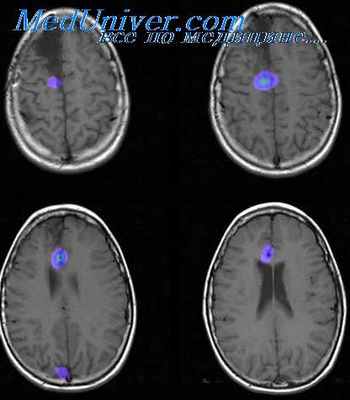

Зона эпилептогенного повреждения — это область структурных изменений в тканях головного мозга. Внутриполушарные и конвекситальные опухоли, каверномы, артериовенозные мальформации и другие структурные изменения могут ассоциироваться с развитием эпилепсии. Такие формы эпилепсии соответственно обозначаются как структурная эпилепсия (ранее — симптоматическая эпилепсия). Для выявления эпилептогенного повреждения проводятся нейровизуализационные исследования.

Таким образом, в функциональной организации эпилептического очага выделяют зоны, определяющие различные составляющие клинико-электрофизиологической картины заболевания: симптоматогенную зону и зону функционального дефицита, ответственные за клинику припадка и постприступное «выпадение»; зону начала приступа и ирритативную зону, которые определяют эпилептиформные изменения на ЭЭГ. Эпилептический очаг формируется, как правило, в результате структурного эпилептогенного повреждения (зона эпилептогенного повреждения), которое выявляется современными нейровизуализационными методами исследований. Основным подходом к локализации эпилептогенной зоны является построение «пересечений» рассматриваемых зон, то есть конкордантность клинических, нейрофизиологических и нейровизуализационных данных.